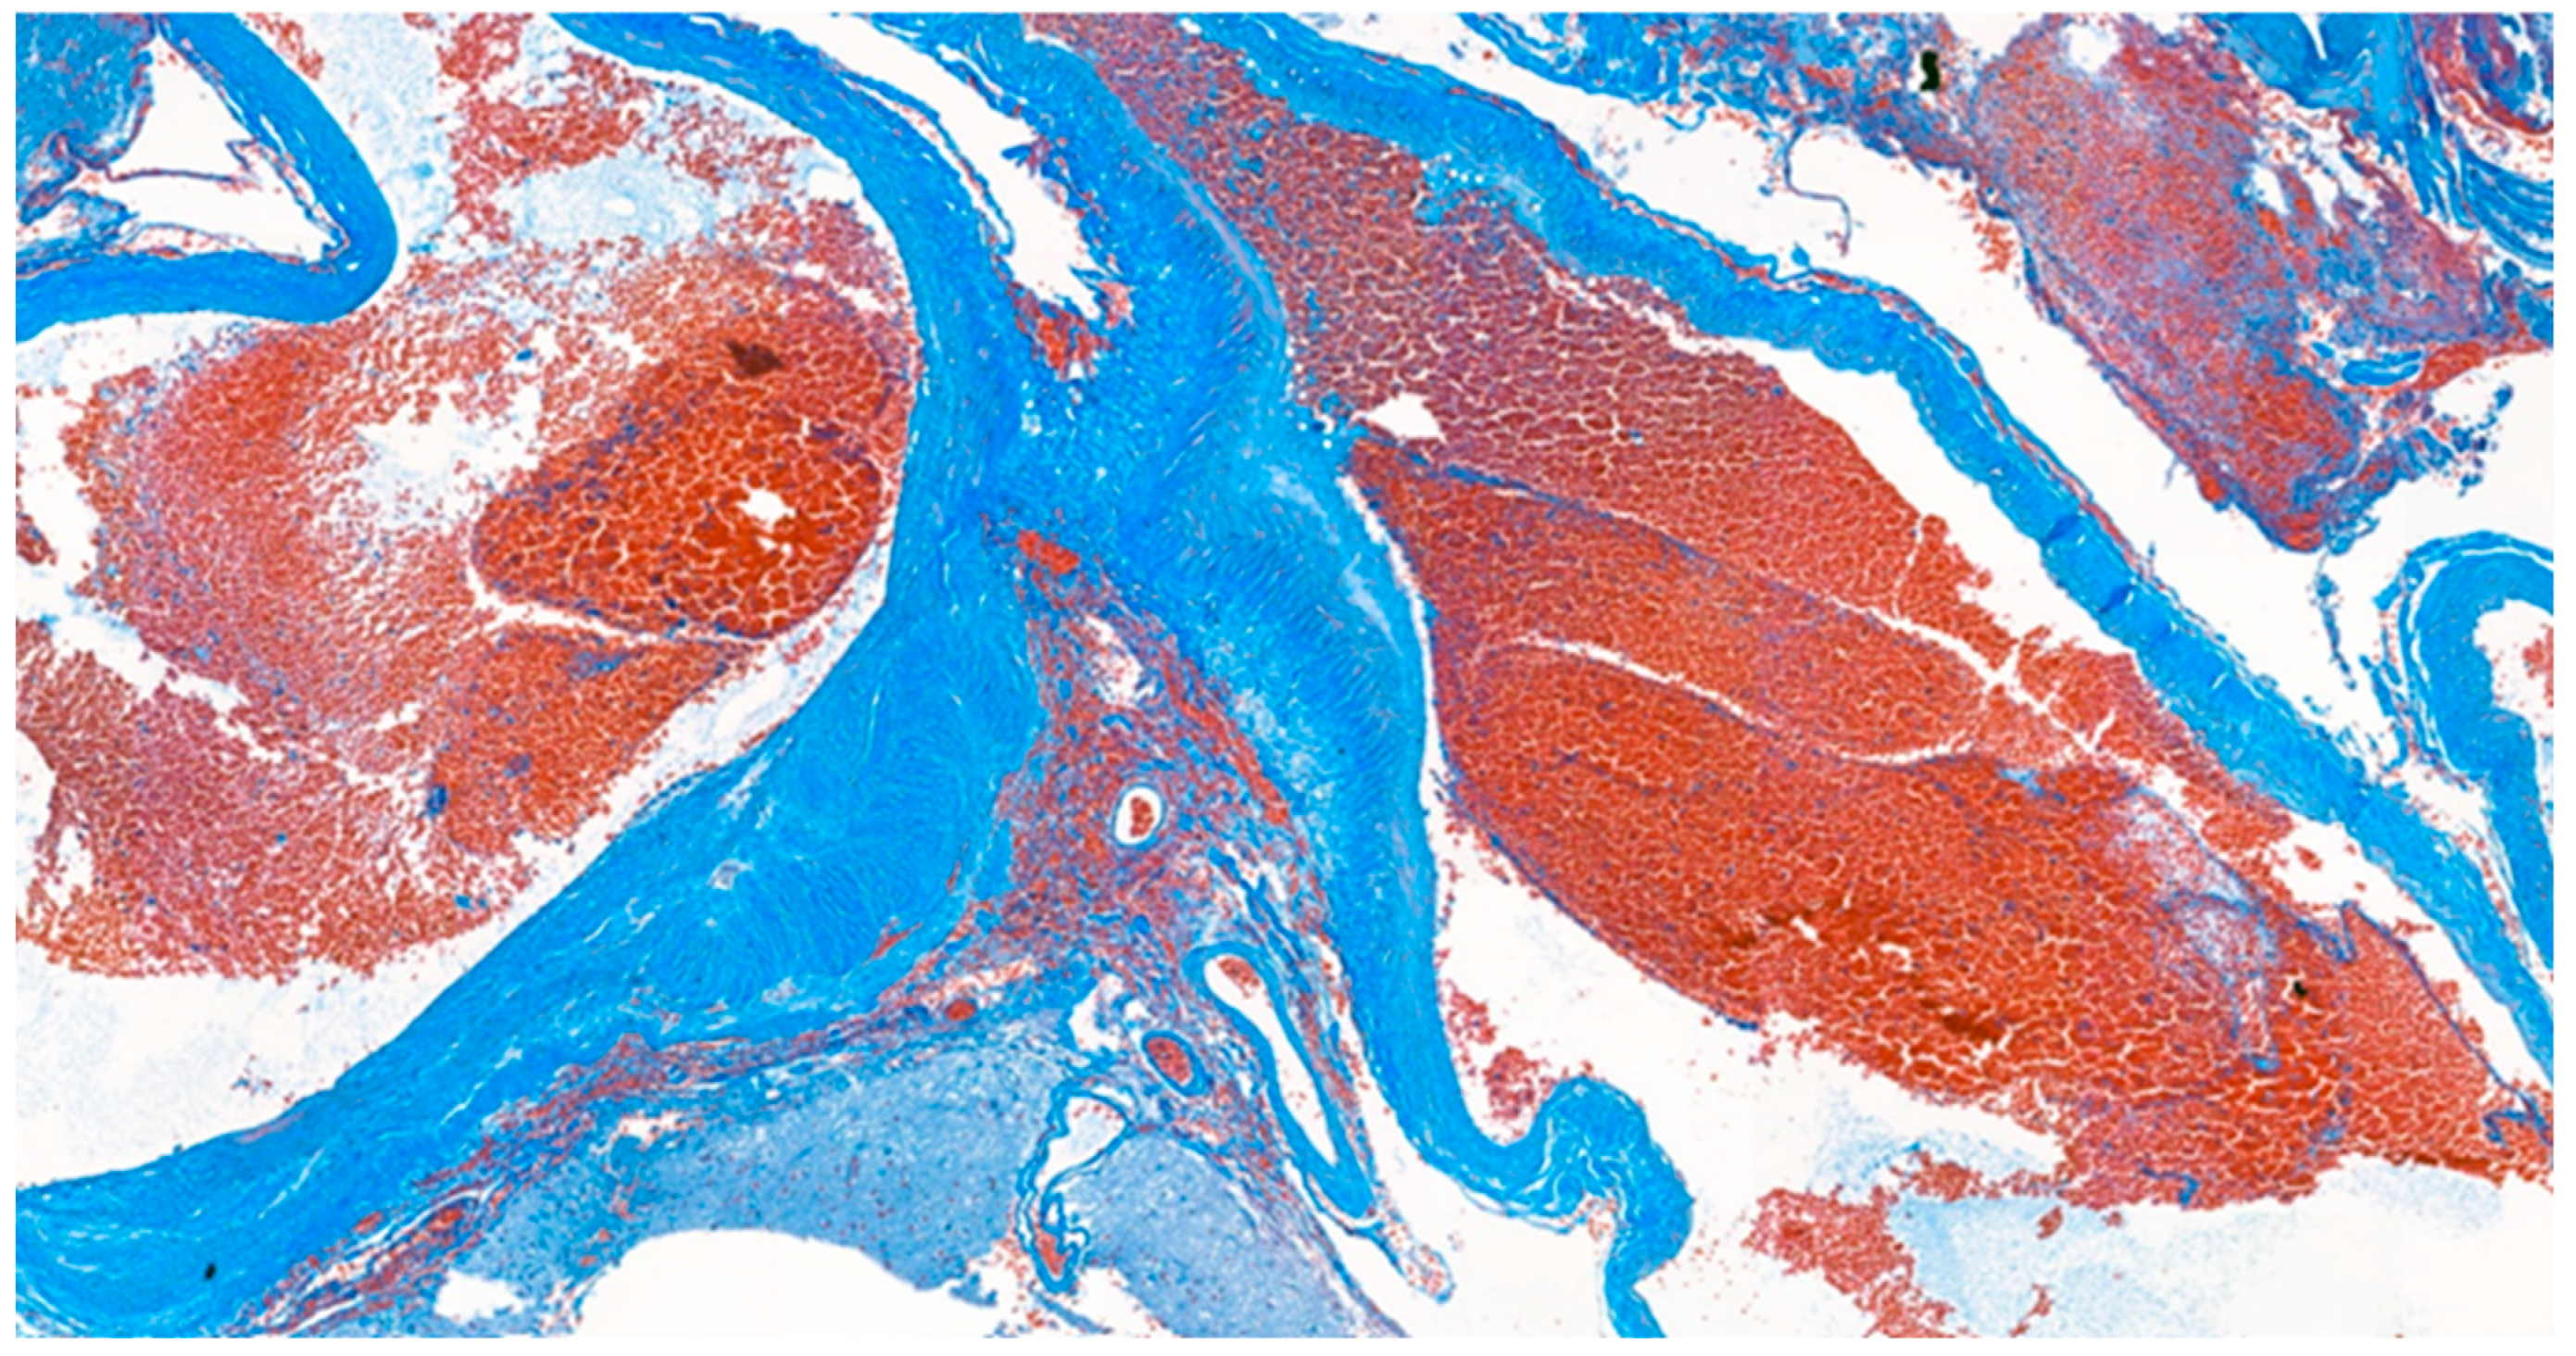

Figure 7.

Masson’s trichrome stain. The histological stain revealed abnormally muscularized arteries.